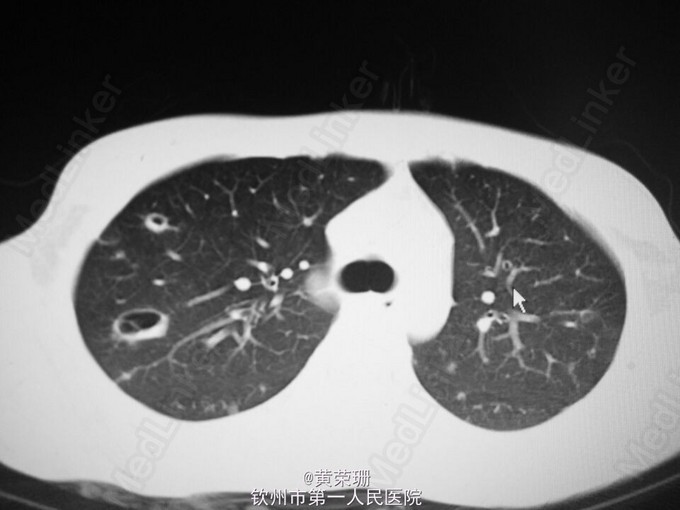

Article "特徴的な心エコー図所見が診断に有用であったレフレル心内膜心筋炎の症例" Detailed information of the J-GLOBAL is an information service managed by the Japan Science and Technology Agency (hereinafter referred to as "JST"). It provides free access to secondary information on researchers, articles, patents, etc., in science and technology, medicine and.. 好酸球増多性心内膜心筋炎. 一いわゆるL6ffler心内膜炎一の1男児例. (平成6年4月26日受付) (平成6年11月28日受理) 1}群馬県立小児医療センター循環器科,現 群馬大学医学部小児科 2)群馬県立小児医療センター循環器科,3)深谷赤十字病院小児科. 小林.

心エコー図検査にて長期間経過観察し得たレフレル心内膜炎の1例

感染性心内膜炎はこんな病気. 感染性心内膜炎とは、「溶血性連鎖球菌 (ようけつせいれんさきゅうきん)」や「ブドウ球菌」、「腸球菌 (ちょうきゅうきん)」、「真菌 (しんきん)」などの菌が、なんらかの原因で血液中に侵入し、心臓内部に感染巣が形成さ.. Article "レフレル心内膜炎および好酸球性心筋炎の発症予測と早期発見方法に関する検討" Detailed information of the J-GLOBAL is an information service managed by the Japan Science and Technology Agency (hereinafter referred to as "JST"). It provides free access to secondary information on researchers, articles, patents, etc., in science and technology, medicine.